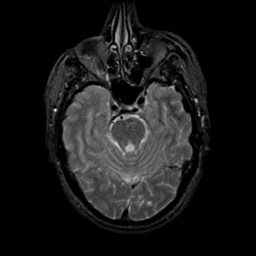

MR Study #9, April 14, 1991 -- Slice #16

[Home][Help][Clinical][Tour 1][Tour 2] Slice 16